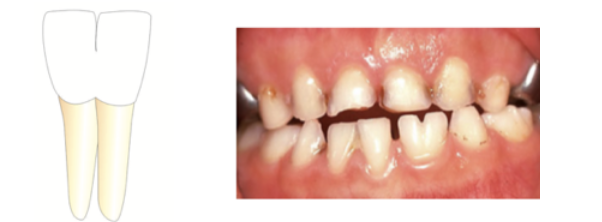

Gemination

1 root buds into 2 crowns

* normal tooth count

* share a root